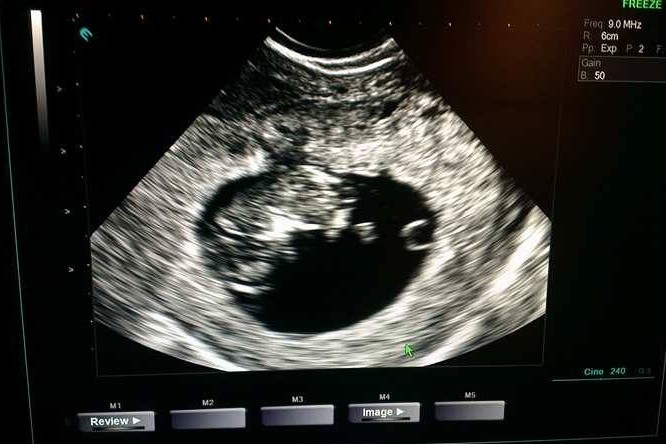

Ja też wczoraj byłam na wizycie. Wszystko ok, ładnie się rozwija.

Co do witamin to mi lekarz kazał brać teraz tylko Folik, a potem od ok 13 tc odstawić i przepisze mi witaminy.

Wstawiam foto :) ma już 28 mm :)